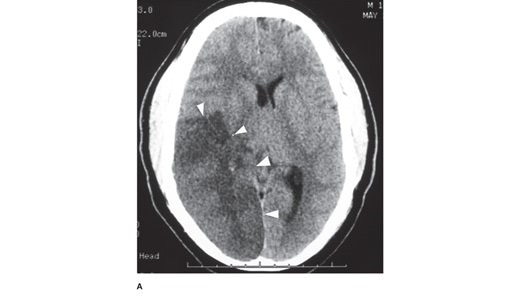

Figure legend: A. Head computed tomography scan of a patient with a 4-day-old stroke that occluded the right middle cerebral and posterior cerebral arteries. The infarcted tissue is the hypodense (dark) area indicated by the arrowheads. The patient presented with left-sided weakness and left visual field loss, but then became less responsive, prompting this head computed tomography. Note the right-to-left midline shift. Neurosurgery, Brunicardi F, Andersen DK, Billiar TR, Dunn DL, Kao LS, Hunter JG, Matthews JB, Pollock RE. Schwartz's Principles of Surgery, 11e; 2019.